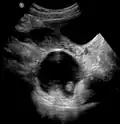

A small (4 cm) dermoid cyst of an ovary, discovered during a C-section

While all ovarian cysts can range in size from very small to quite large, dermoid cysts are not classified as functional cysts. Dermoid cysts originate from pluripotent germ cells (which are present at birth) that differentiate abnormally, developing characteristics of mature dermal cells. Complications exist, such as torsion (twisting), rupture, and infection, although their incidence is rare. Dermoid ovarian cysts which are larger present complications which might require removal by either laparoscopy or laparotomy (traditional surgery).[3][4] Rarely, a dermoid cyst can develop in the vagina.[5][6][7]